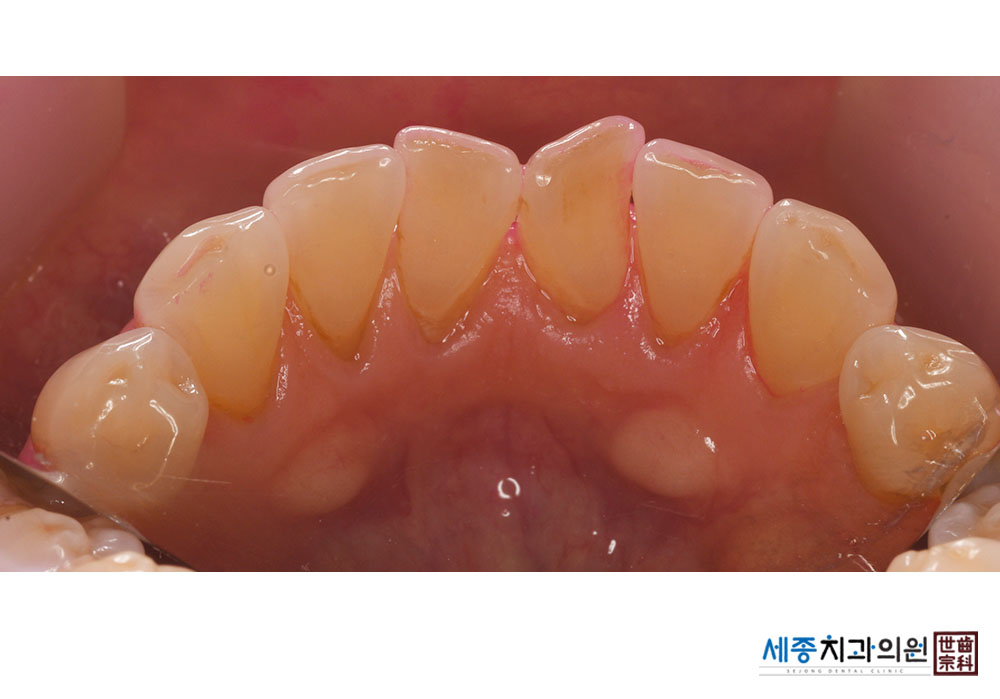

[스케일링] 치주질환 예방 스케일링

치료후 : 2020-01-29

가글마취&저주파 스켈러를 사용한 스케일링